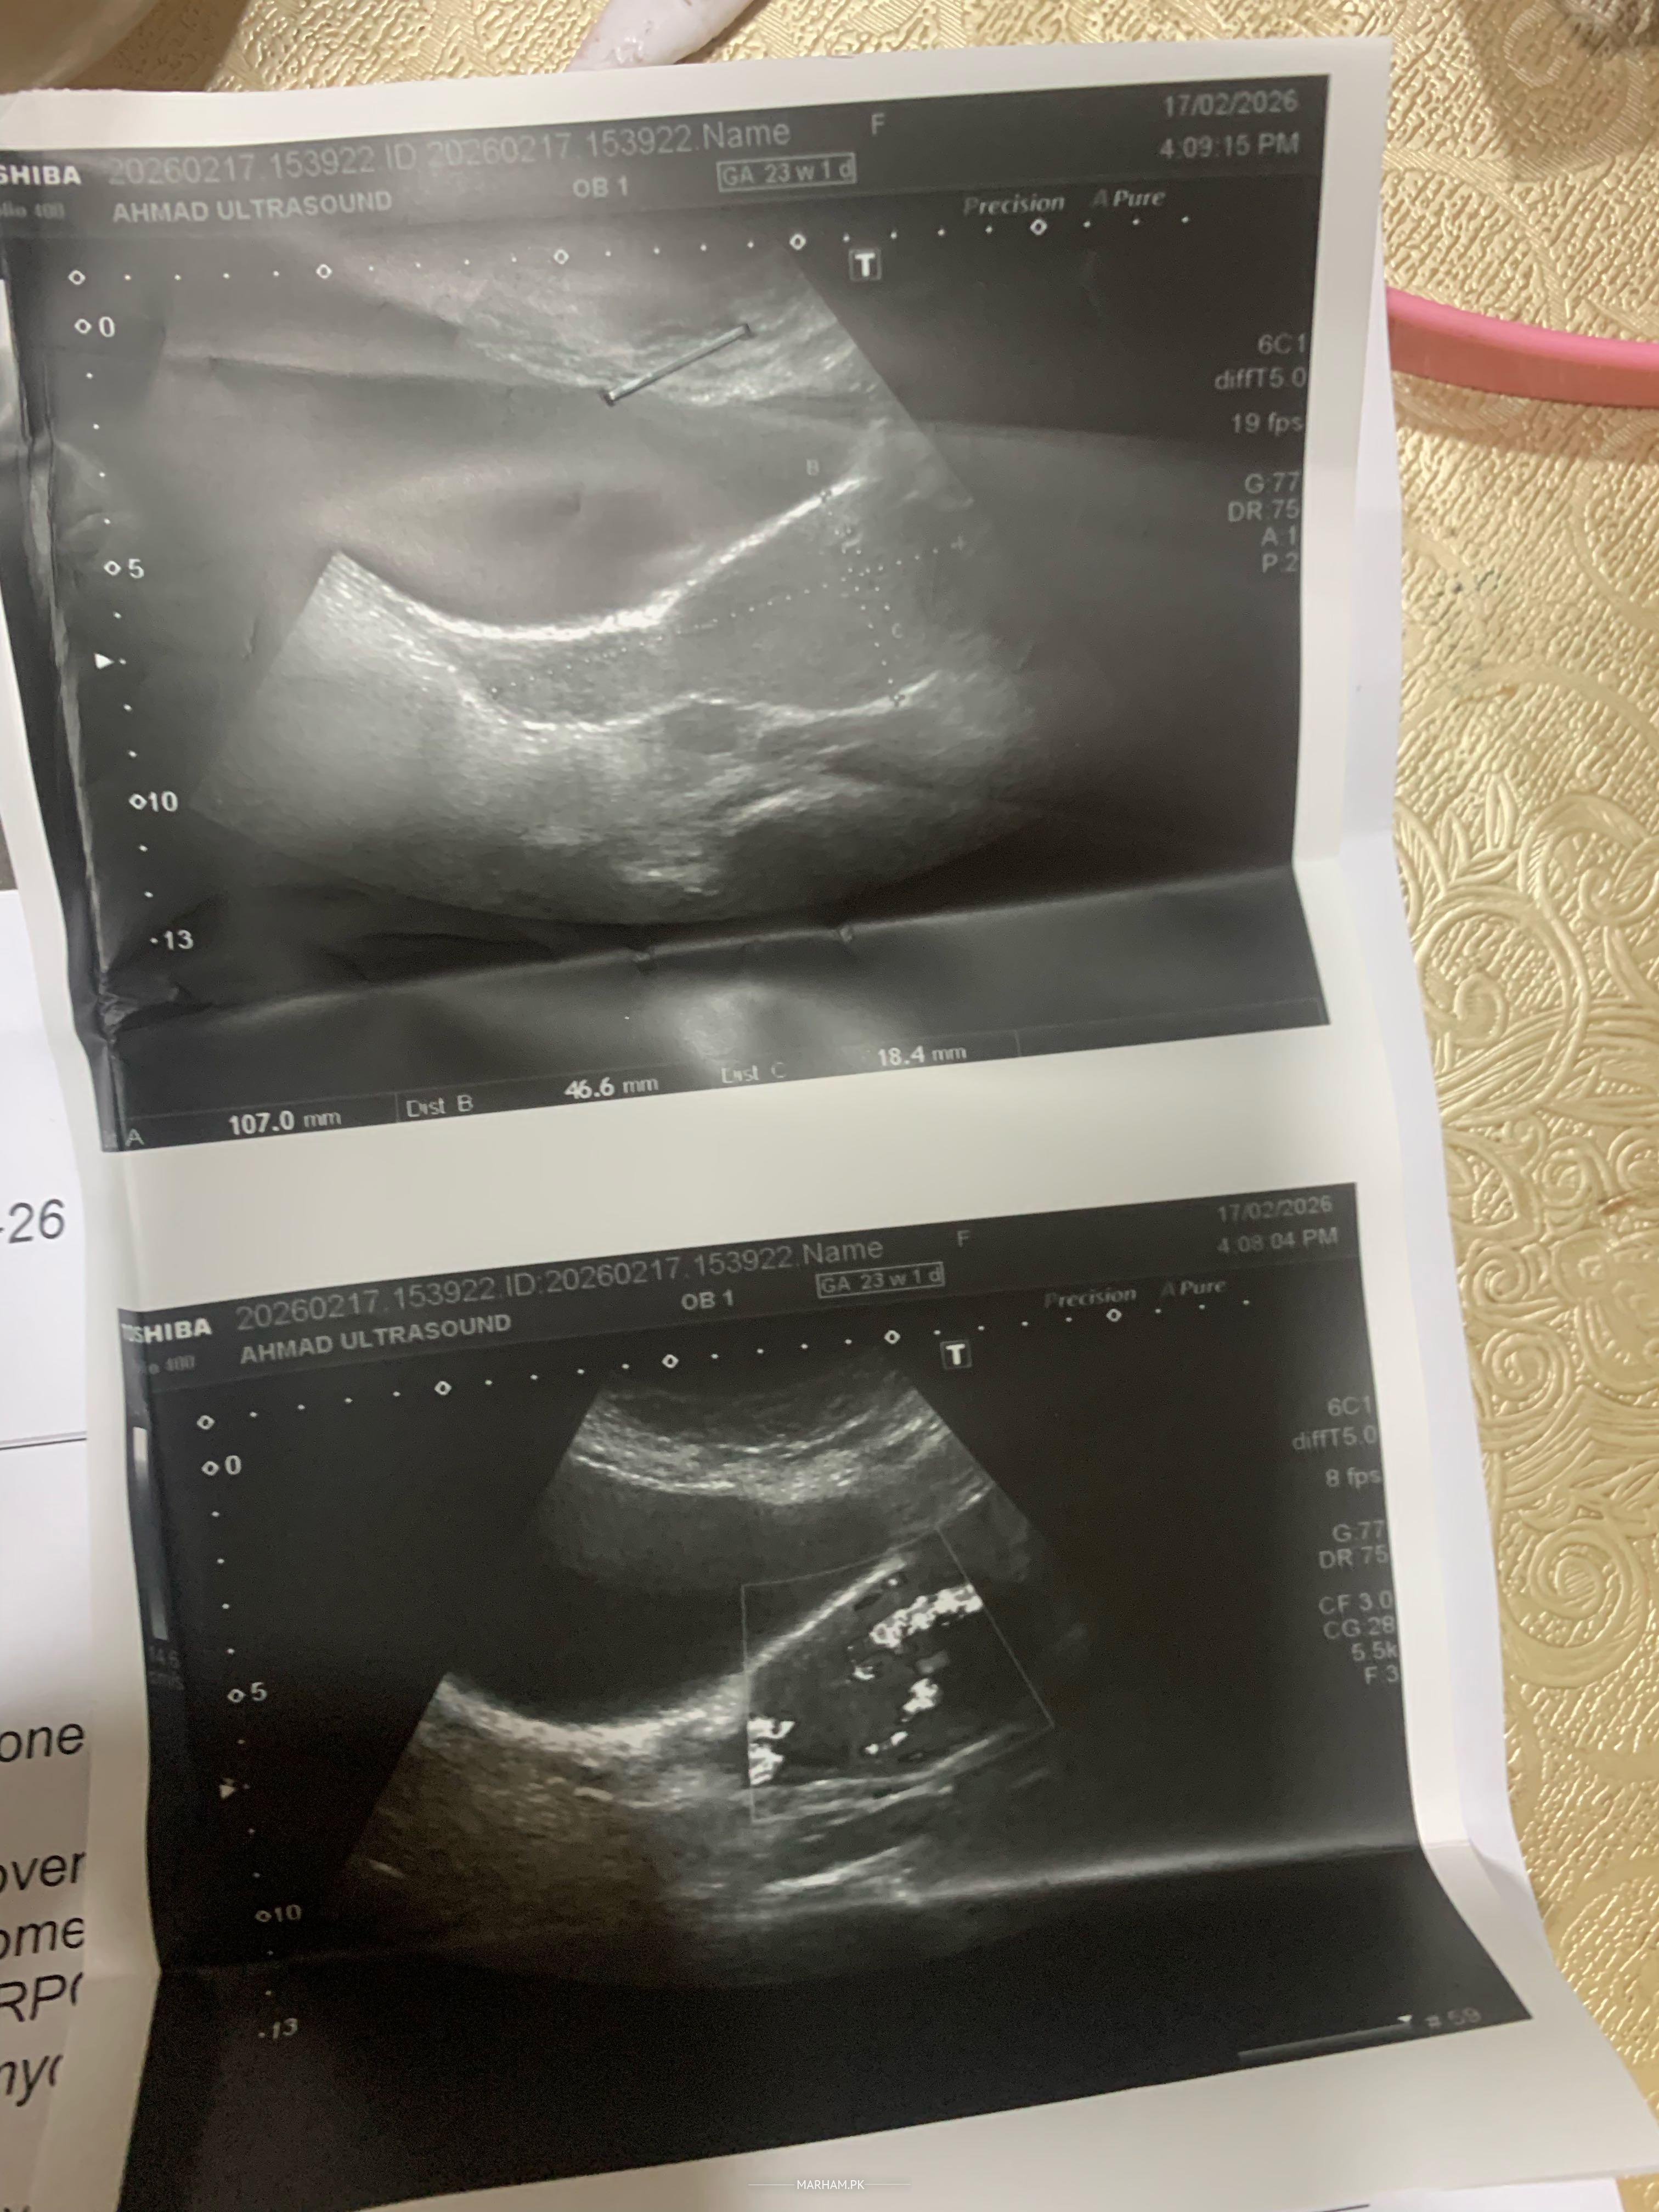

On 10th January, I had a miscarriage. After that, I used tablets, but it did not clear completely. Then I went for another scan, and after that scan, it was found that there were RPOCs (retained products of conception). Now I have had another scan on 10th February, after one month. The report is in front of you. Please suggest to me whether I should go for D&C, because internally there are no RPOCs, but this report is in front of you. Please suggest what I should do. I am scared of d&C

consultant radiologist se ultrasound krwaen. Sath main doppler bhi. do not go for dnc. it can lead to heavy bleeding

should have scan from radiologist and have a clear statement about rpocs. do beta HCG and then repeat after a week

No tissue left. Evaluation not needed

Get your Doppler ultrasound done then consult

Immediately Get serum beta HCG n share plz